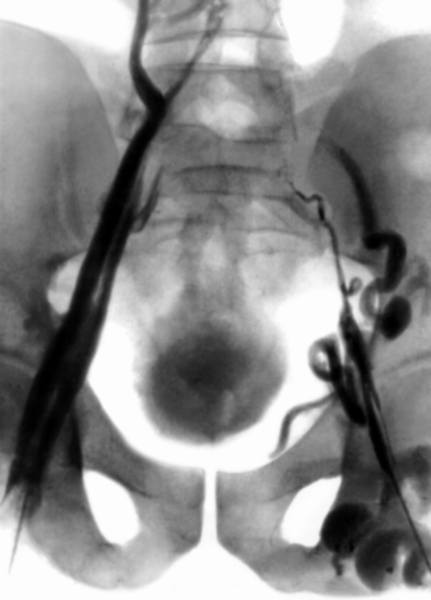

Тазовая флебограмма при окклюзии нижней полой вены

Распознавание тромбоза инфраренального сегмента нижней полой вены (с распространением этого процесса на подвздошные вены и окклюзией дистальных притоков) не вызывает особых затруднений при быстром нарастании отека и цианоза нижних конечностей, наружных половых органов и нижней половины тела в сочетании с острой болью в подвздошных, паховых и поясничной областях. Появление усиленного венозного рисунка на передней брюшной стенке при некотором уменьшении плотного отека подкожной клетчатки спустя несколько дней служит дополнительным диагностическим признаком. Для верификации диагноза используют специальные методы исследования и, прежде всего, кавографию.